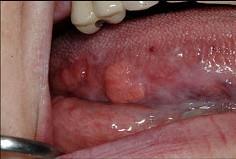

以下关于舌癌(如图)的叙述,哪项是错误的 ( )

- A.舌根部癌可向茎突后及咽后部的淋巴转移

- B.以鳞状细胞癌多见

- C.转移途径多为直接浸润和种植转移

- D.常发生早期颈部淋巴结转移

- E.多发生于舌缘,恶性程度高

C